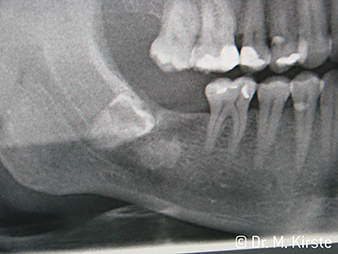

W&H Пример с пациент

Фиг. 7:

... е внимателно отстранен с новия обратен наконечник.